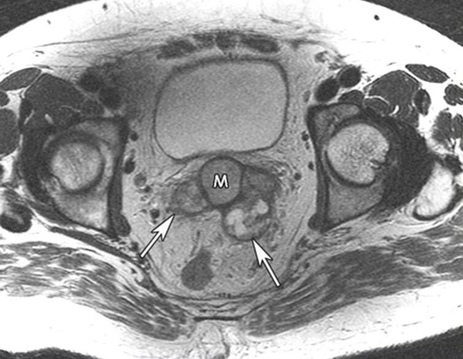

- УЗИ простаты и семенных пузырьков. Является надежным методом для раннего обнаружения опухолей.

- КТ и генитография, трансперинеальная везикулография с пункцией. Оказываются полезными в оценке степени распространения патологического процесса и для дифференцирования его от воспалительных заболеваний, обструктивных состояний и связанных с ними осложнений.